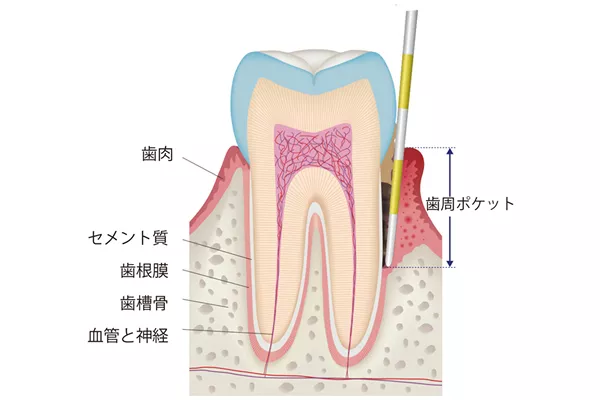

厚生労働省による令和4年の調査結果によると、人口の全体の47.9%の歯周ポケット(歯周病の進行の指標となる歯と歯の間の溝、健康状態だと1~2mm)が4mm以上だとされています。これは歯周病の初期症状であるとされています。

歯周ポケットの深さは、歯周病の進行度合いを示す指標となります。健康な歯茎の場合1~2mmである歯周ポケットの深さが、3~4mmを超えた場合は、歯周病が進行している可能性が高くなり、注意が必要です。